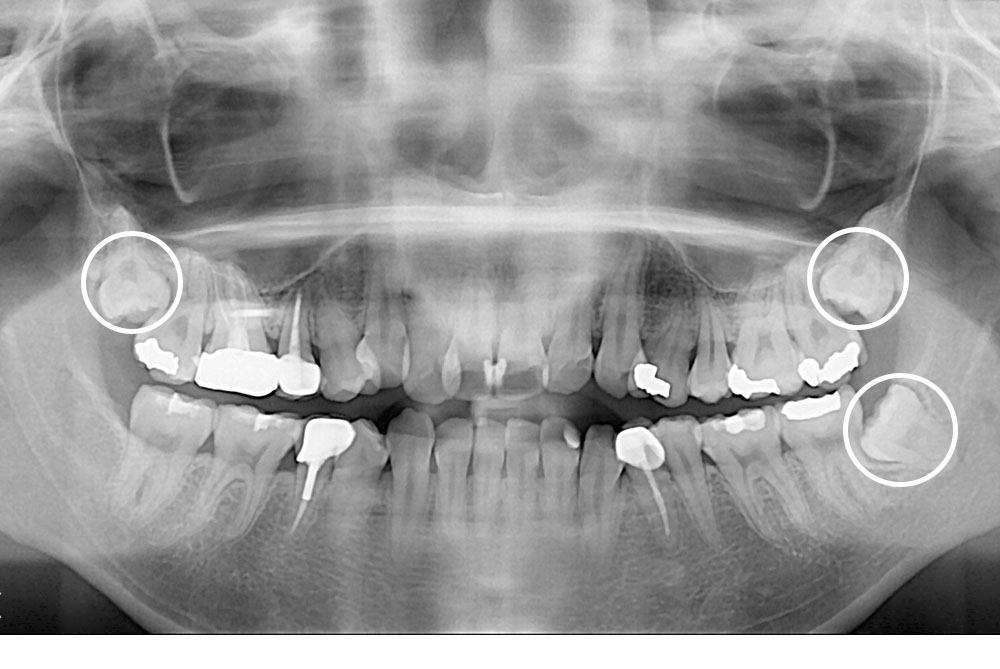

[사랑니] 매복 사랑니 발치

치료후 : 2017-10-18

세종치과는 구강악안면외과학 박사이신 원장님이 발치하는 치과입니다.